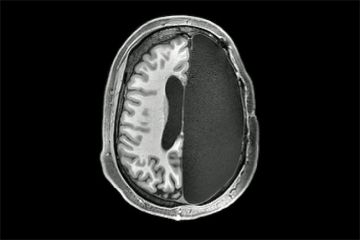

Mạn phép cắt bỏ "cô bé" của bệnh nhân chuyển giới, bác sĩ bị treo bằng

Thứ Sáu, 28/02/2020Người đàn ông - chuyển giới từ một người phụ nữ, đã khóc đẫm nước mắt sau cuộc phẫu thuật chuyển đổi giới tính không thể làm lại được, phiên tòa xét xử cho hay.